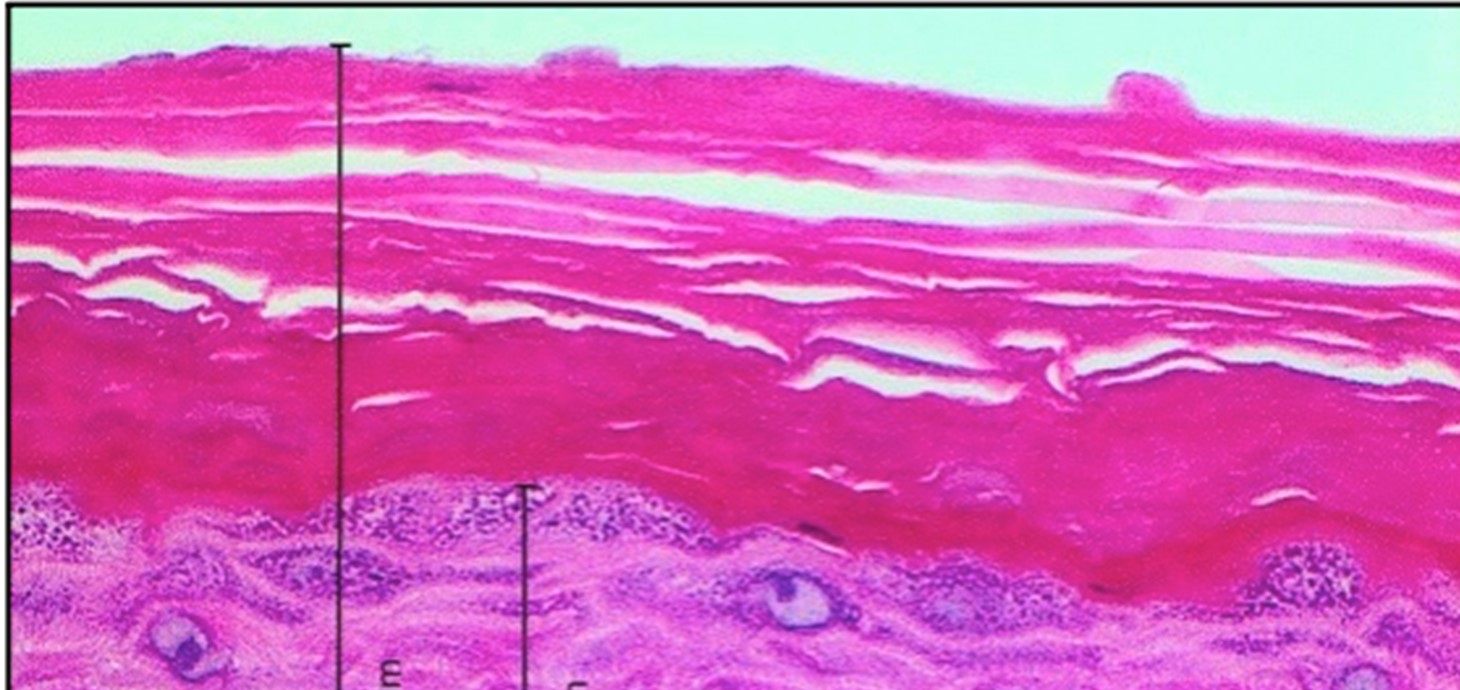

Cross-section through reconstructed human skin, cultured in the laboratory, used to test the safety of products applied to the skin. Research by the Swansea-led CALIN project, which works closely with companies.

The Celtic Advanced Life Science Innovation Network (CALIN) of three Welsh and three Irish universities, led by Swansea University, underlines the importance of research to local industry.  This project offers research and development opportunities to SMEs in the sector, providing open access to life science experts and facilities.  It has been funded by the ERDF and the Ireland-Wales EU Funds programme.

CALIN scientists have worked with Virustatic, which develops protein-based solutions for a range of industries, including medicines, feminine health and antimicrobial textiles, which means less reliance on harmful and polluting chemical compounds. Their best-known product is the Virustatic® SHIELD, a breakthrough in viral filtration technology, which won the MediWales Innovation Award.